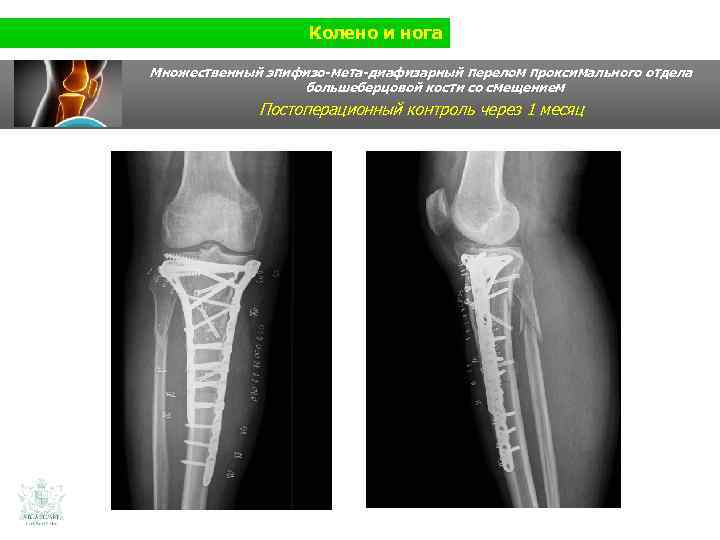

Колено и нога Множественный эпифизо-мета-диафизарный перелом проксимального отдела большеберцовой кости со смещением Постоперационный контроль через 1 месяц